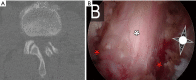

Figures